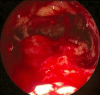

Endonasal endoscopic sinus surgery is the standard procedure for surgery of most paranasal sinus diseases. Appropriate frame conditions provided, the respective procedures are safe and successful. These prerequisites encompass appropriate technical equipment, anatomical oriented surgical technique, proper patient selection, and individually adapted extent of surgery. The range of endonasal sinus operations has dramatically increased during the last 20 years and reaches from partial uncinectomy to pansinus surgery with extended surgery of the frontal (Draf type III), maxillary (grade 3-4, medial maxillectomy, prelacrimal approach) and sphenoid sinus. In addition there are operations outside and beyond the paranasal sinuses. The development of surgical technique is still constantly evolving. This article gives a comprehensive review on the most recent state of the art in endoscopic sinus surgery according to the literature with the following aspects: principles and fundamentals, surgical techniques, indications, outcome, postoperative care, nasal packing and stents, technical equipment.